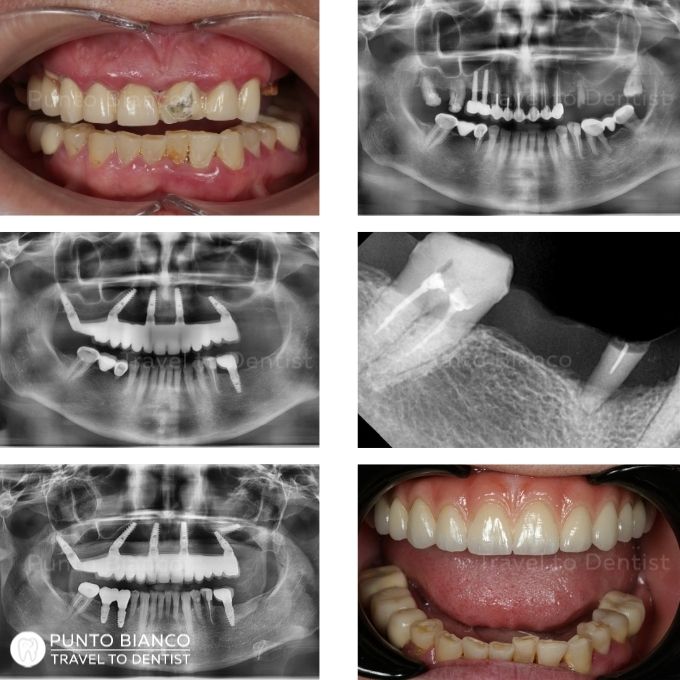

Fotografii înainte și după Restaurări

Problema

Soluția

Tratamentul a fost realizat printr-o soluție echilibrată, cu accent pe estetică și cost controlat. Dinții irecuperabili și sursele de infecție au fost îndepărtate, iar zonele edentate au fost reabilitate prin implanturi și coroane metalo-ceramice. Pentru dinții frontali s-au realizat restaurări estetice directe din compozit, cu efect de tip fațete, pentru a îmbunătăți rapid forma și aspectul zâmbetului.

Durata

Tratamentul a fost realizat în 2 vizite: prima a durat 7 zile, iar a doua 12 zile.